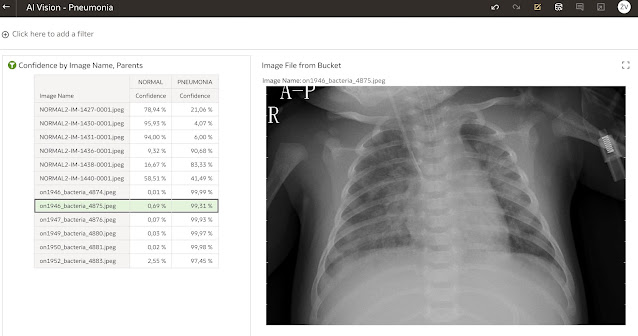

The left part of the visualisation is a simple pivot table containing image name and location and confidence for Pneumonia or Normal lungs.

However for the right part Vision Series plug-in is used. Let’s take a look at it.

Visualisation's parameters for our example are rather simple. We are showing only one image at the time, and Image File from Bucket is located in Image Location field. If we were using this visualisation component for object detection, then object coordinates would be put into Vertices field.

As image is displayed one by one (always is displayed the 1st from the list), the pivot table visualisation is used as a filter.